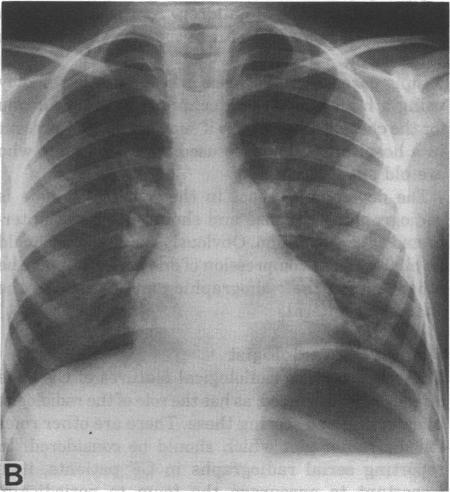

The chest radiograph in cystic fibrosis in children and the role of other radiological techniques.

J R Soc Med. 1987;80 Suppl 15(Suppl 15):38-46.

原文链接:https://pmc.ncbi.nlm.nih.gov/articles/PMC1290612/